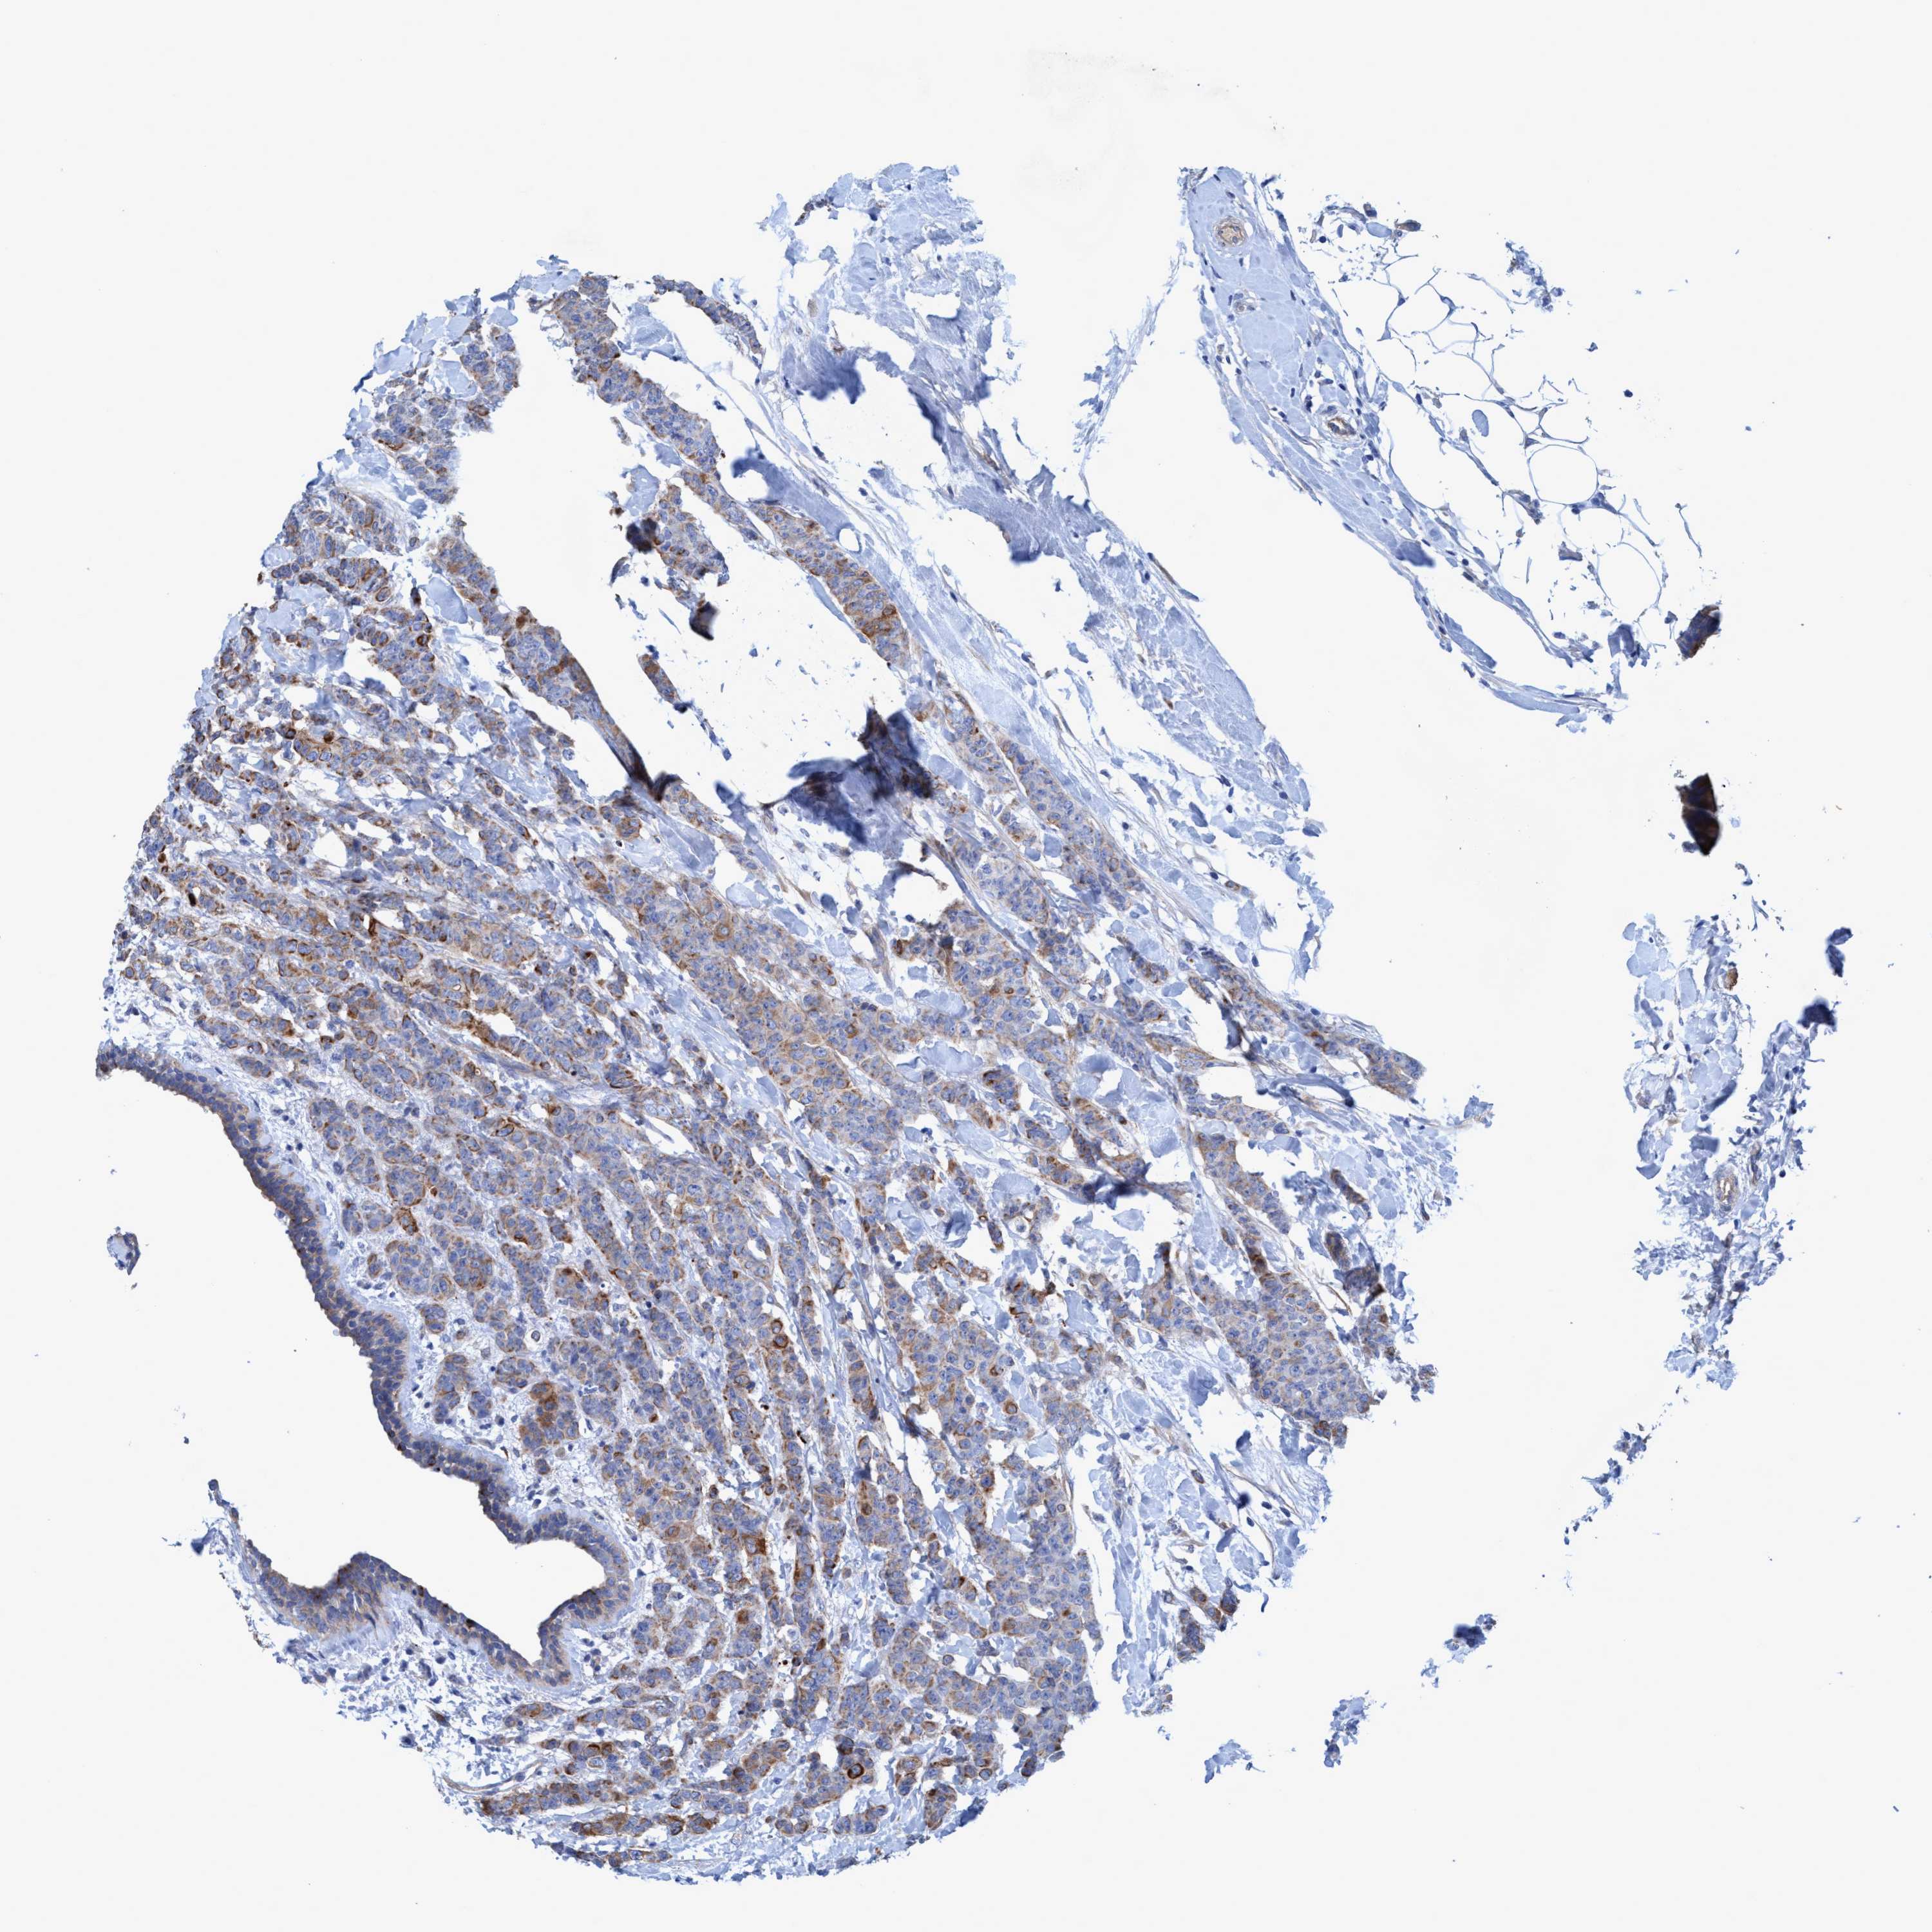

BRCA TCGA BRCA VALIDATION PROTEIN EXPRESSION

ANTIBODIES

AND

VALIDATION